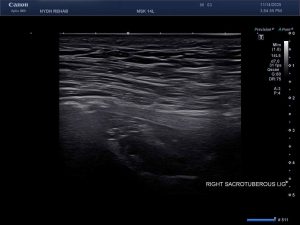

Ultrasound Images of SIJ Ligaments

• Sacrotuberous ligament thickening and enthesopathy